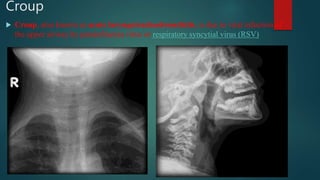

Croup

 Croup, also known as acute laryngotracheobronchitis, is due to viral infection of

the upper airway by parainfluenza virus or respiratory syncytial virus (RSV)

• #126 Characteristic tapering of the upper trachea (steeple sign) on an AP radiograph which was suspicious for croup in this clinical context. Lateral x-ray of the neck demonstrates distension of hypopharynx and subglottic oedema consistent with croup.